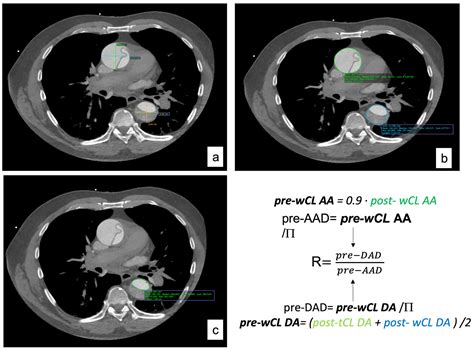

CT Angiography (CTA) Uses contrast dye to create detailed 3D images of the aorta.

Surgery is typically recommended when the diameter of the aorta exceeds specific thresholds—usually 5.0 cm to 5.5 cm, depending on the patient’s underlying genetic risk factors. Surgical options involve replacing the dilated segment with a synthetic graft to reinforce the vessel wall and prevent rupture.